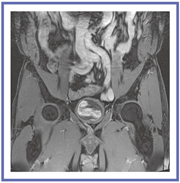

Enhanced Fat Freeは,Titan 3Tに搭載された脂肪抑制技術である。脂肪選択的に90°以上の励起を行い,Spoiler Gradientによって横磁化成分を分散し,残存する縦磁化成分に再度脂肪選択的に90°励起を行いSpoiler Gradientにより脂肪成分からの信号を分散し,均一な脂肪抑制効果を得る方法である。Enhanced Fat Freeによって,前立腺のダイナミックスタディでも均一な脂肪抑制が得られており,造影効果もはっきりと確認できる。これはFOVの大きな冠状断の場合でも同様で,広範囲かつ均一で良好な脂肪抑制が実現されている(図3)。